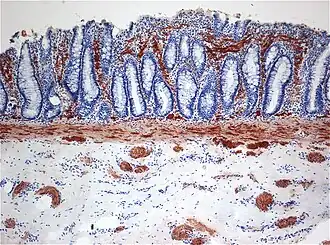

Le diagnostic repose essentiellement sur la biopsie intestinale du rectum. Le médecin prélève un fragment du rectum et l’examine ; en l'absence de cellule ganglionnaire et en cas d'hypertrophie des fibres nerveuses parasympathiques la maladie de Hirschsprung est diagnostiquée.